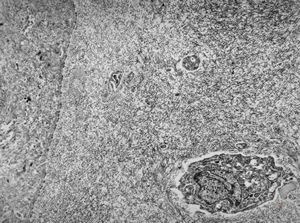

F,72y. | melanoblastoma oculi